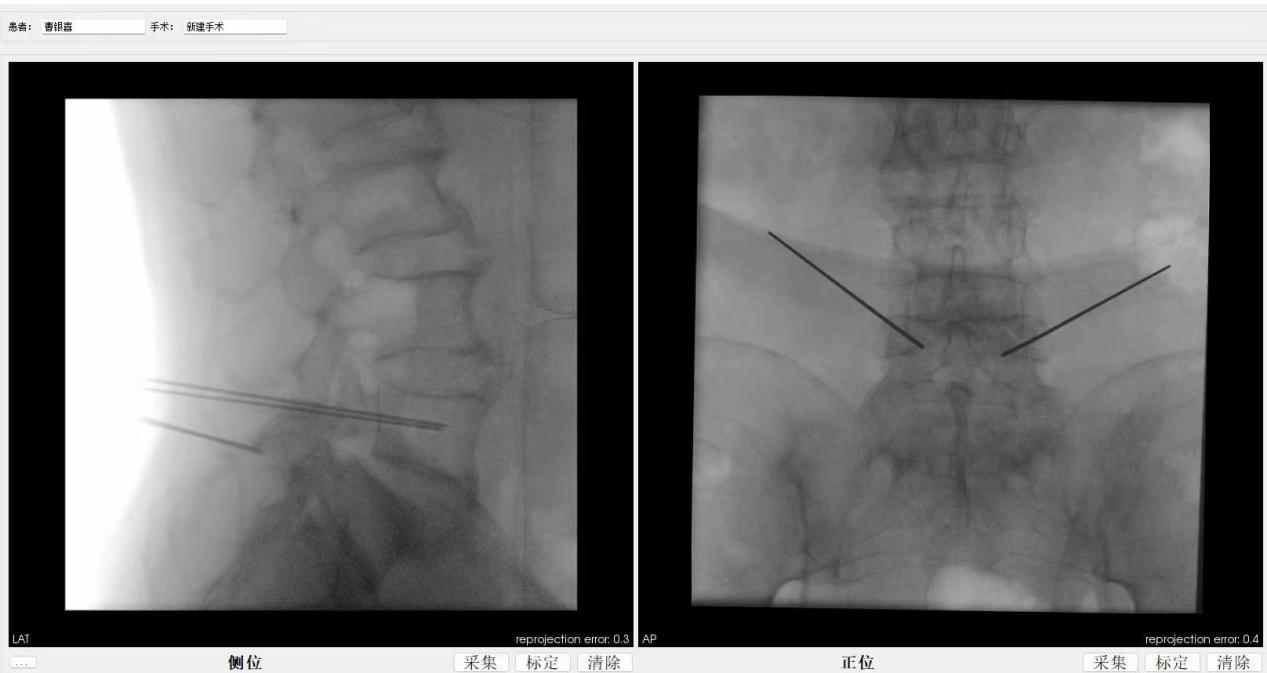

ORTHBOT脊柱机器人术前设计及术中穿刺

,均建议采取传统外科开放手术治疗,患者因担心手术风险,迟迟不愿手术。经多方打听,患者慕名找到李全义主任医师。入院后李全义主任医师仔细研究患者的疾病特点,经过充分的沟通,决定采用目前骨科先进的微创、精准技术—机器人辅助微创手术。李全义主任医师团队顺利为患者实施ORTHBOT脊柱机器人辅助镜下腰5椎体滑脱复位椎管减压椎间融合内固定术,以机器人辅助微创手术解决了患者的痛苦,减少手术创伤及并发症,缩短手术时间。手术利用术前患者的影像学资料,模拟建立穿刺路径及各项参数,极大地优化手术方案使其更加精准、安全、有效,显著降低了制钉过程中神经根损伤的风险。